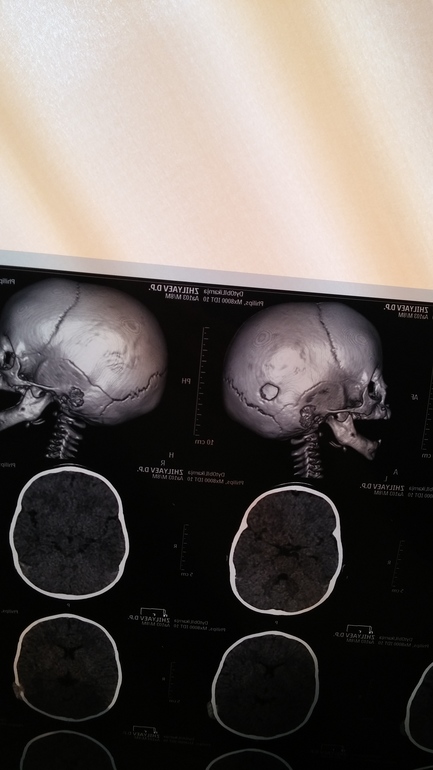

Трепанация черепа в 8 месяцев